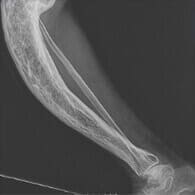

Suyaklarning deformatsiyasi

Ikki yil tirsakim dahshatli og‘ridi, shifokorga borishga vaqt topolmadim. Dorilar bilan qandaydir kurashdim, biroz yengil bo‘lar edi, keyin tirsakda bursa singari tugun paydo bo‘ldi. Juda vahimaga tushdim! Xotinimga rahmat, meni to‘liq davolanishga undadi va Flexoderil olib keldi. To‘liq kursni yakunladim, shish ketdi, og‘riq butunlay yo‘qoldi. Nihoyat o‘zimni haqiqiy erkakdek his qilyapman!

Tizzam ostida kista borligi aniqlangan, shifokor hech nima qila olmasligini, uni olib tashlash mumkin emasligini aytdi. Boshqa shifokorga bordim, u Flexoderil ni kuniga ikki marta qo‘llashni tavsiya qildi. Darhol yengillik sezildi, uch hafta ichida og‘riq butunlay yo‘qoldi. Yarim yildan so‘ng kista ajoyib tarzda so‘nib ketgani ma’lum bo‘ldi!